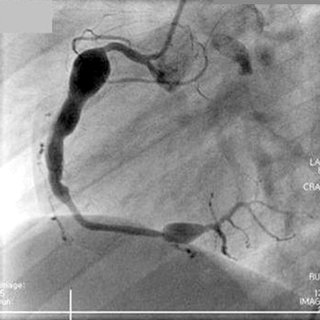

심장 및 혈관계의 관상동맥류가 가장 심각한 합병증입니다.

관상동맥은 심장을 먹여 살리는 혈관으로, 여기에 혈관꽈리, 혈관류가 발생합니다.

거대 관상동맥류로 직경이 8mm 이상크기가 발생하여, 파열되거나,

혈전형성에 의해서 심근경색의 위험이 발생합니다.

이러한 관상동맥류는 가와사키가 제대로 치료되지 않는 경우 20%에서 발생하여,

생명을 위협하게되고, 오랜 발열이 되는 경우는 관상동맥 합병증의 위험요인이 됩니다.